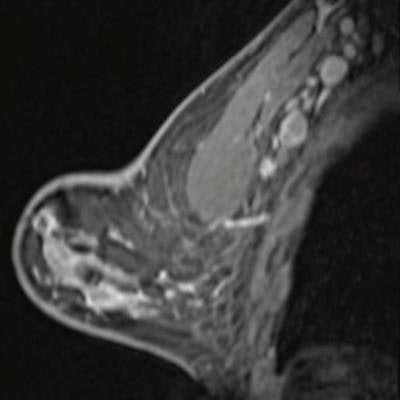

Breast MRI after first COVID-19 vaccination dose. Image courtesy of the American Roentgen Ray Society.

Breast MRI after first COVID-19 vaccination dose. Image courtesy of the American Roentgen Ray Society.Radiology continues to play a pivotal role in responding to the COVID-19 crisis, as the second finalist for Scientific Paper of the Year showed by warning that vaccines can manifest on imaging in ways that mimic disease.

Dr. Shabnam Mortazavi of the University of California, Los Angeles called for practice recommendations to prevent excessive follow-up imaging and potential biopsy of COVID-19 vaccination-associated axillary adenopathy.

In the study of 23 women who underwent breast imaging after being vaccinated, researchers found that most of the adenopathy on breast imaging occurred with the Pfizer vaccine (52%), among asymptomatic women presenting for either screening or diagnostic purposes (86%), and on ultrasound (52%).

Incorporating a patient's COVID-19 vaccination history, including vaccination date and laterality, is critical to optimize assessment and management of imaging-detected axillary adenopathy in women with otherwise normal breast imaging, Mortazavi stated.